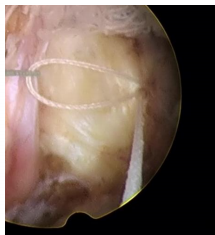

一次性纖維環(huán)縫合器的臨床應(yīng)用:

隨著纖維環(huán)縫合器縫合纖維環(huán)技術(shù)的推廣,很多學(xué)者做了相關(guān)的臨床研究。Parker等對30例纖維環(huán)縫合患者進(jìn)行了2年隨訪研究,零復(fù)發(fā)且椎間隙高度無改變。Bailey等通過對750名患者對比研究,發(fā)現(xiàn)纖維環(huán)非縫合組在術(shù)后2年時的再手術(shù)率較縫合組高45%。研究發(fā)現(xiàn),縫合纖維環(huán)可提高椎間盤生物力學(xué)性能,縮短其愈合時間,同時也減緩椎間盤組織的退變進(jìn)程。修復(fù)后纖維環(huán)回縮可減少對神經(jīng)根刺激,可有效消除疼痛癥狀。目前LDH髓核摘除術(shù)后復(fù)發(fā)的主要病因為纖維環(huán)缺損、持續(xù)重復(fù)應(yīng)力因素等,比較明確的病因為手術(shù)導(dǎo)致的纖維環(huán)缺損,總結(jié)得出髓核突出少、纖維環(huán)缺損嚴(yán)重者術(shù)后的復(fù)發(fā)率高。縫合后纖維細(xì)胞受到反復(fù)牽拉應(yīng)力刺激,可促進(jìn)纖維環(huán)的愈合和防止炎癥因子的產(chǎn)生。纖維環(huán)愈合產(chǎn)生的瘢痕組織可減輕關(guān)節(jié)突關(guān)節(jié)的應(yīng)力作用。縫合纖維環(huán)可提高術(shù)后髓核“再水化”,促進(jìn)腰椎功能恢復(fù)。纖維環(huán)縫合益處:閉合裂口;降低術(shù)后復(fù)發(fā)率及再手術(shù)率;減輕髓核組織的免疫學(xué)反應(yīng)和炎癥介質(zhì)的外滲;有利于髓核的再生修復(fù)。要點:切口大小以5mm的線形縱切口較佳,8mm以上需平行或交叉縫合2針;縫合針距離邊緣2~3mm為宜;縫合前,應(yīng)行邊緣探查,尋求無佳的縫合點。目前纖維環(huán)縫合面臨的重要問題是如何改善或降低縫合處的應(yīng)力積累,受應(yīng)力積累影響瘢痕組織及神經(jīng)纖維可能侵入椎間盤,可引起盤源性疼痛。有學(xué)者對比研究得出,單針簡單縫合,可降低術(shù)后復(fù)發(fā)率,雙針交叉或平行縫合療效更好,而改良荷包縫合,術(shù)后能避免髓核再次突出,生物力學(xué)完整性可得到更好保留。

一次性纖維環(huán)縫合器手術(shù)中注意事項:

①適度增大開窗,便于縫合器的擺放及調(diào)整;

②切開纖維環(huán)時避免傷及內(nèi)側(cè)的神經(jīng)根及硬膜囊;

③摘除髓核時,避免損傷切口兩側(cè)的纖維環(huán),盡量保留纖維環(huán)殘端的長度和厚度以便于縫合;

④縫合時,纖維環(huán)縫合器的扳機(jī)應(yīng)朝向術(shù)者對側(cè),避免因扳機(jī)遮擋影響術(shù)中穿刺;

⑤直針穿刺時旋鈕要旋轉(zhuǎn)到位,標(biāo)志線對齊,避免打成空結(jié);

6.?從纖維環(huán)切口的中1/3 處縱向縫合,避免縫線一側(cè)。